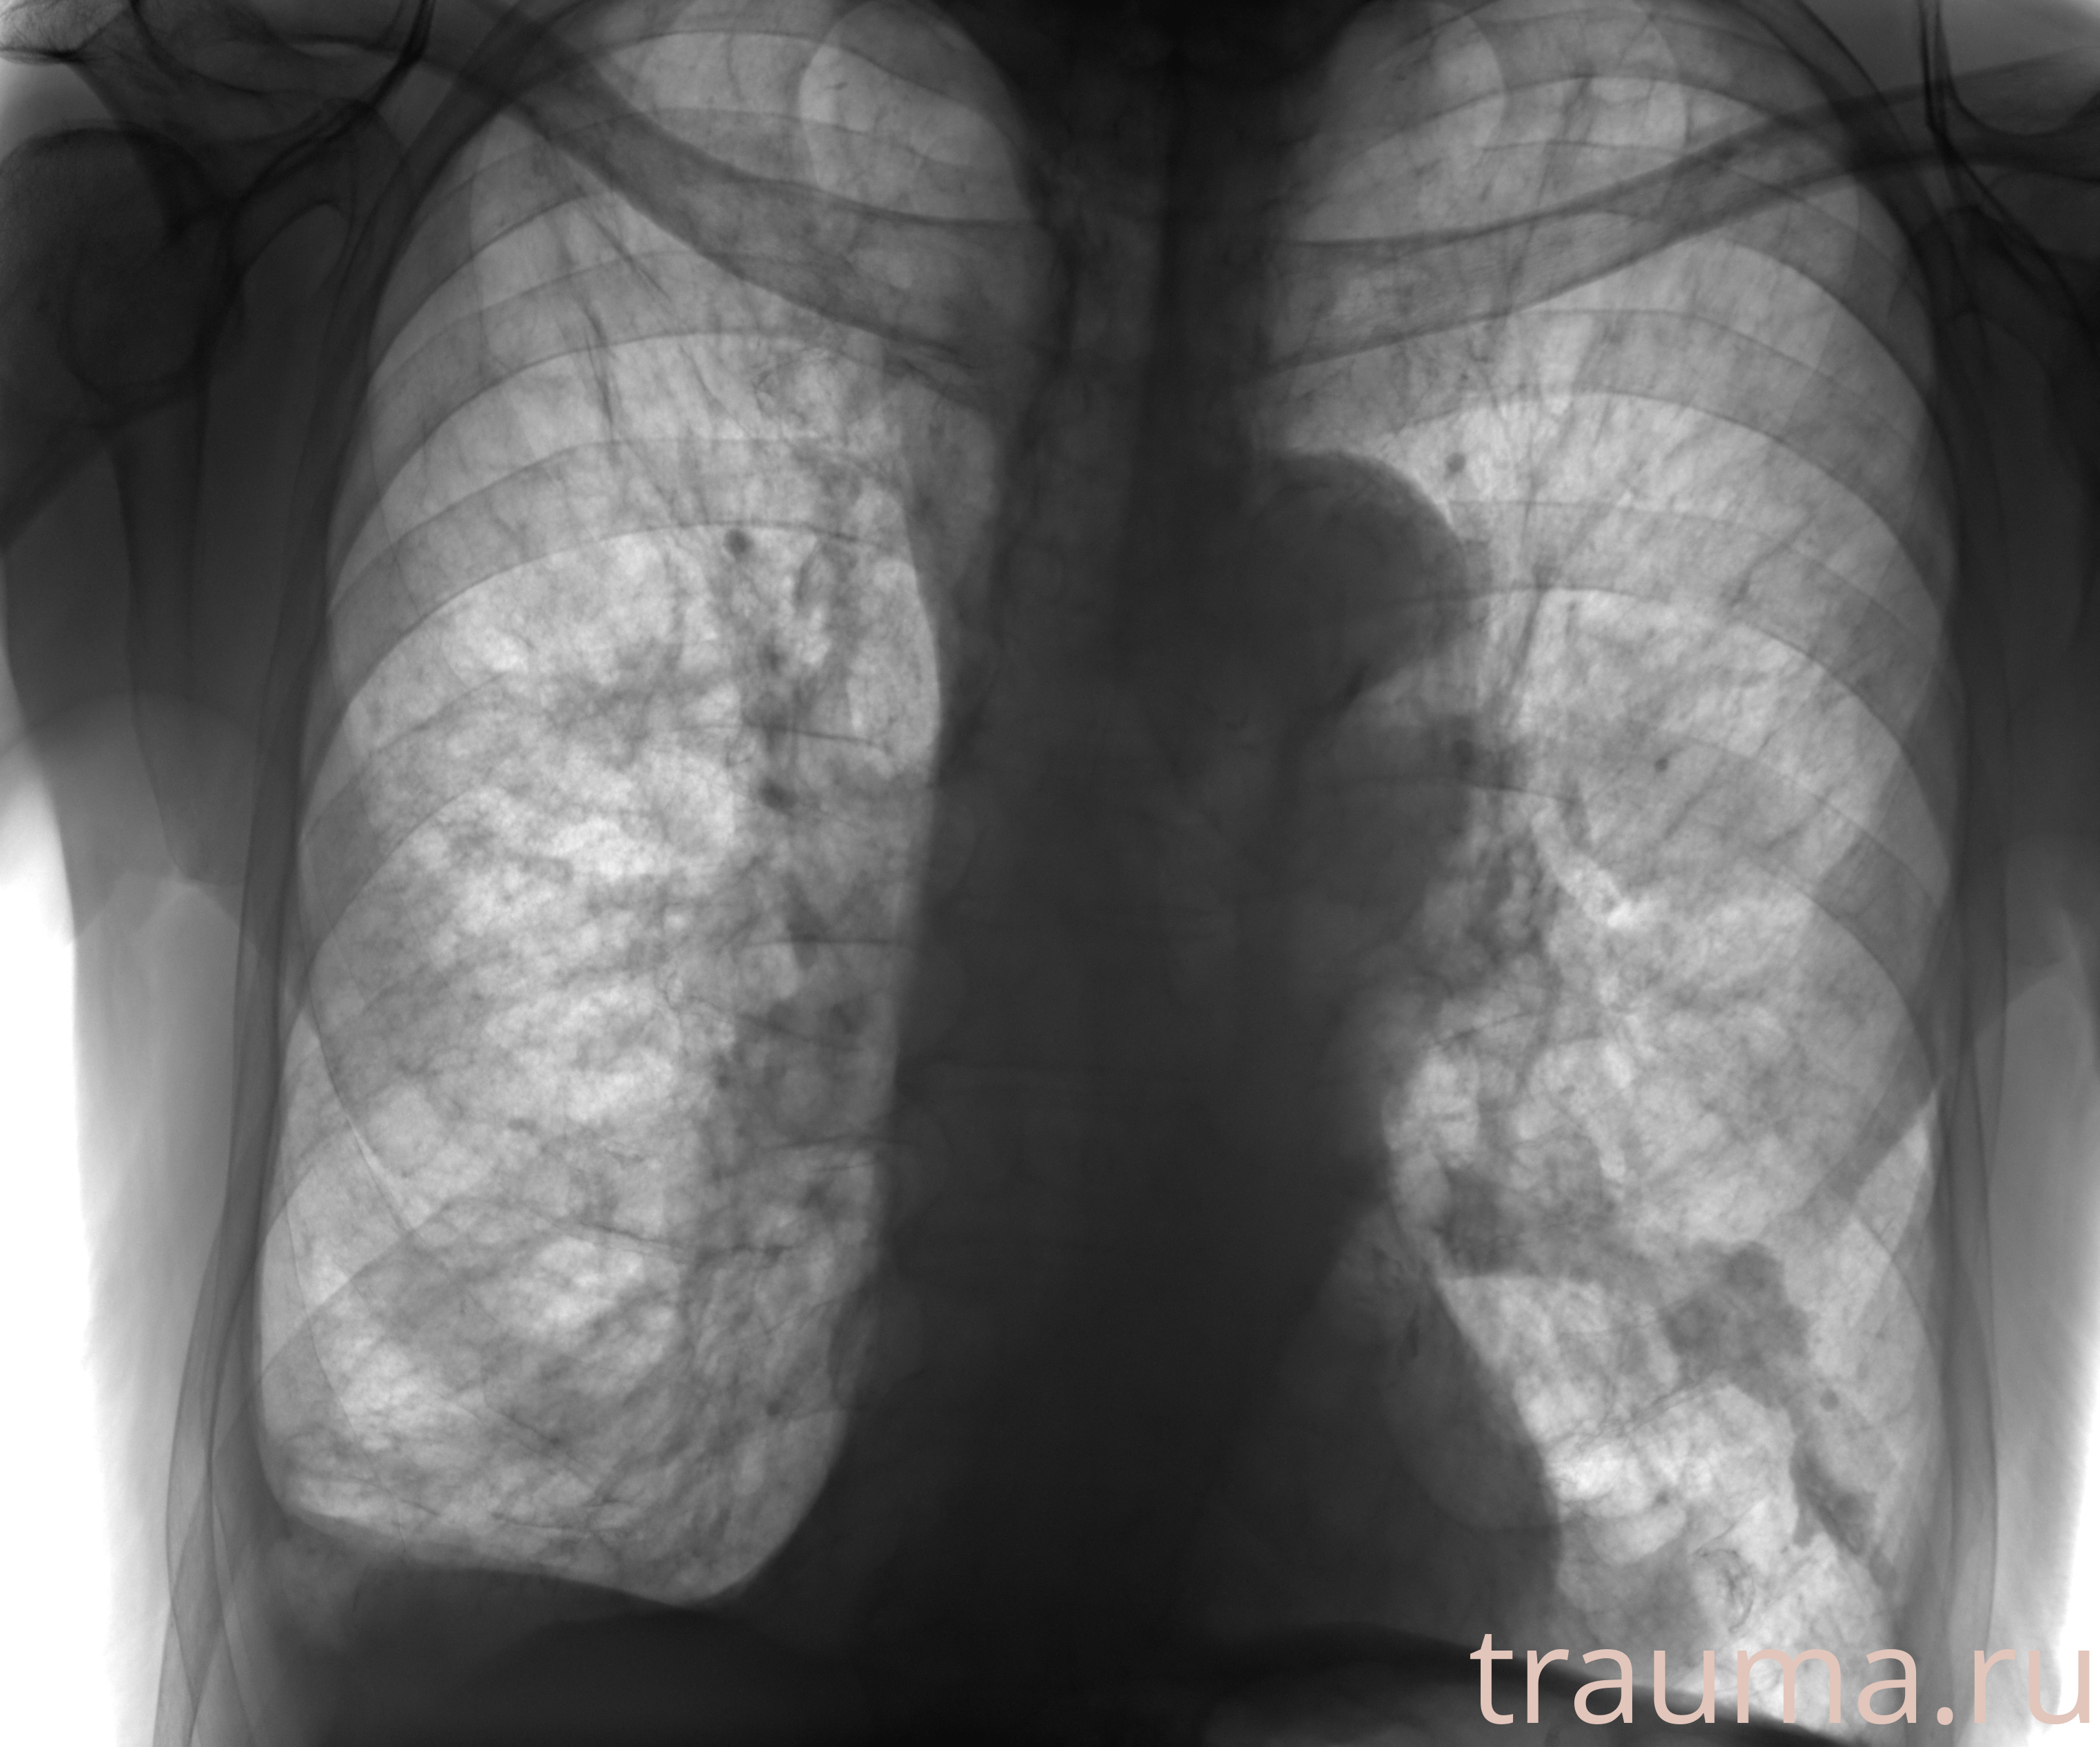

Рентгенограммы

Рентген на дому: по вашему адресу приезжает врач-рентгенолог, травматолог-ортопед с мобильным рентгеновским аппаратом, проводит диагностику травмы или заболевания, делает необходимые рентгенограммы, дает рекомендации по дальнейшему лечению. Получить качественные снимки в домашних условиях возможно благодаря уникальной методике, разработанной МосРентген Центром для института  Склифосовского